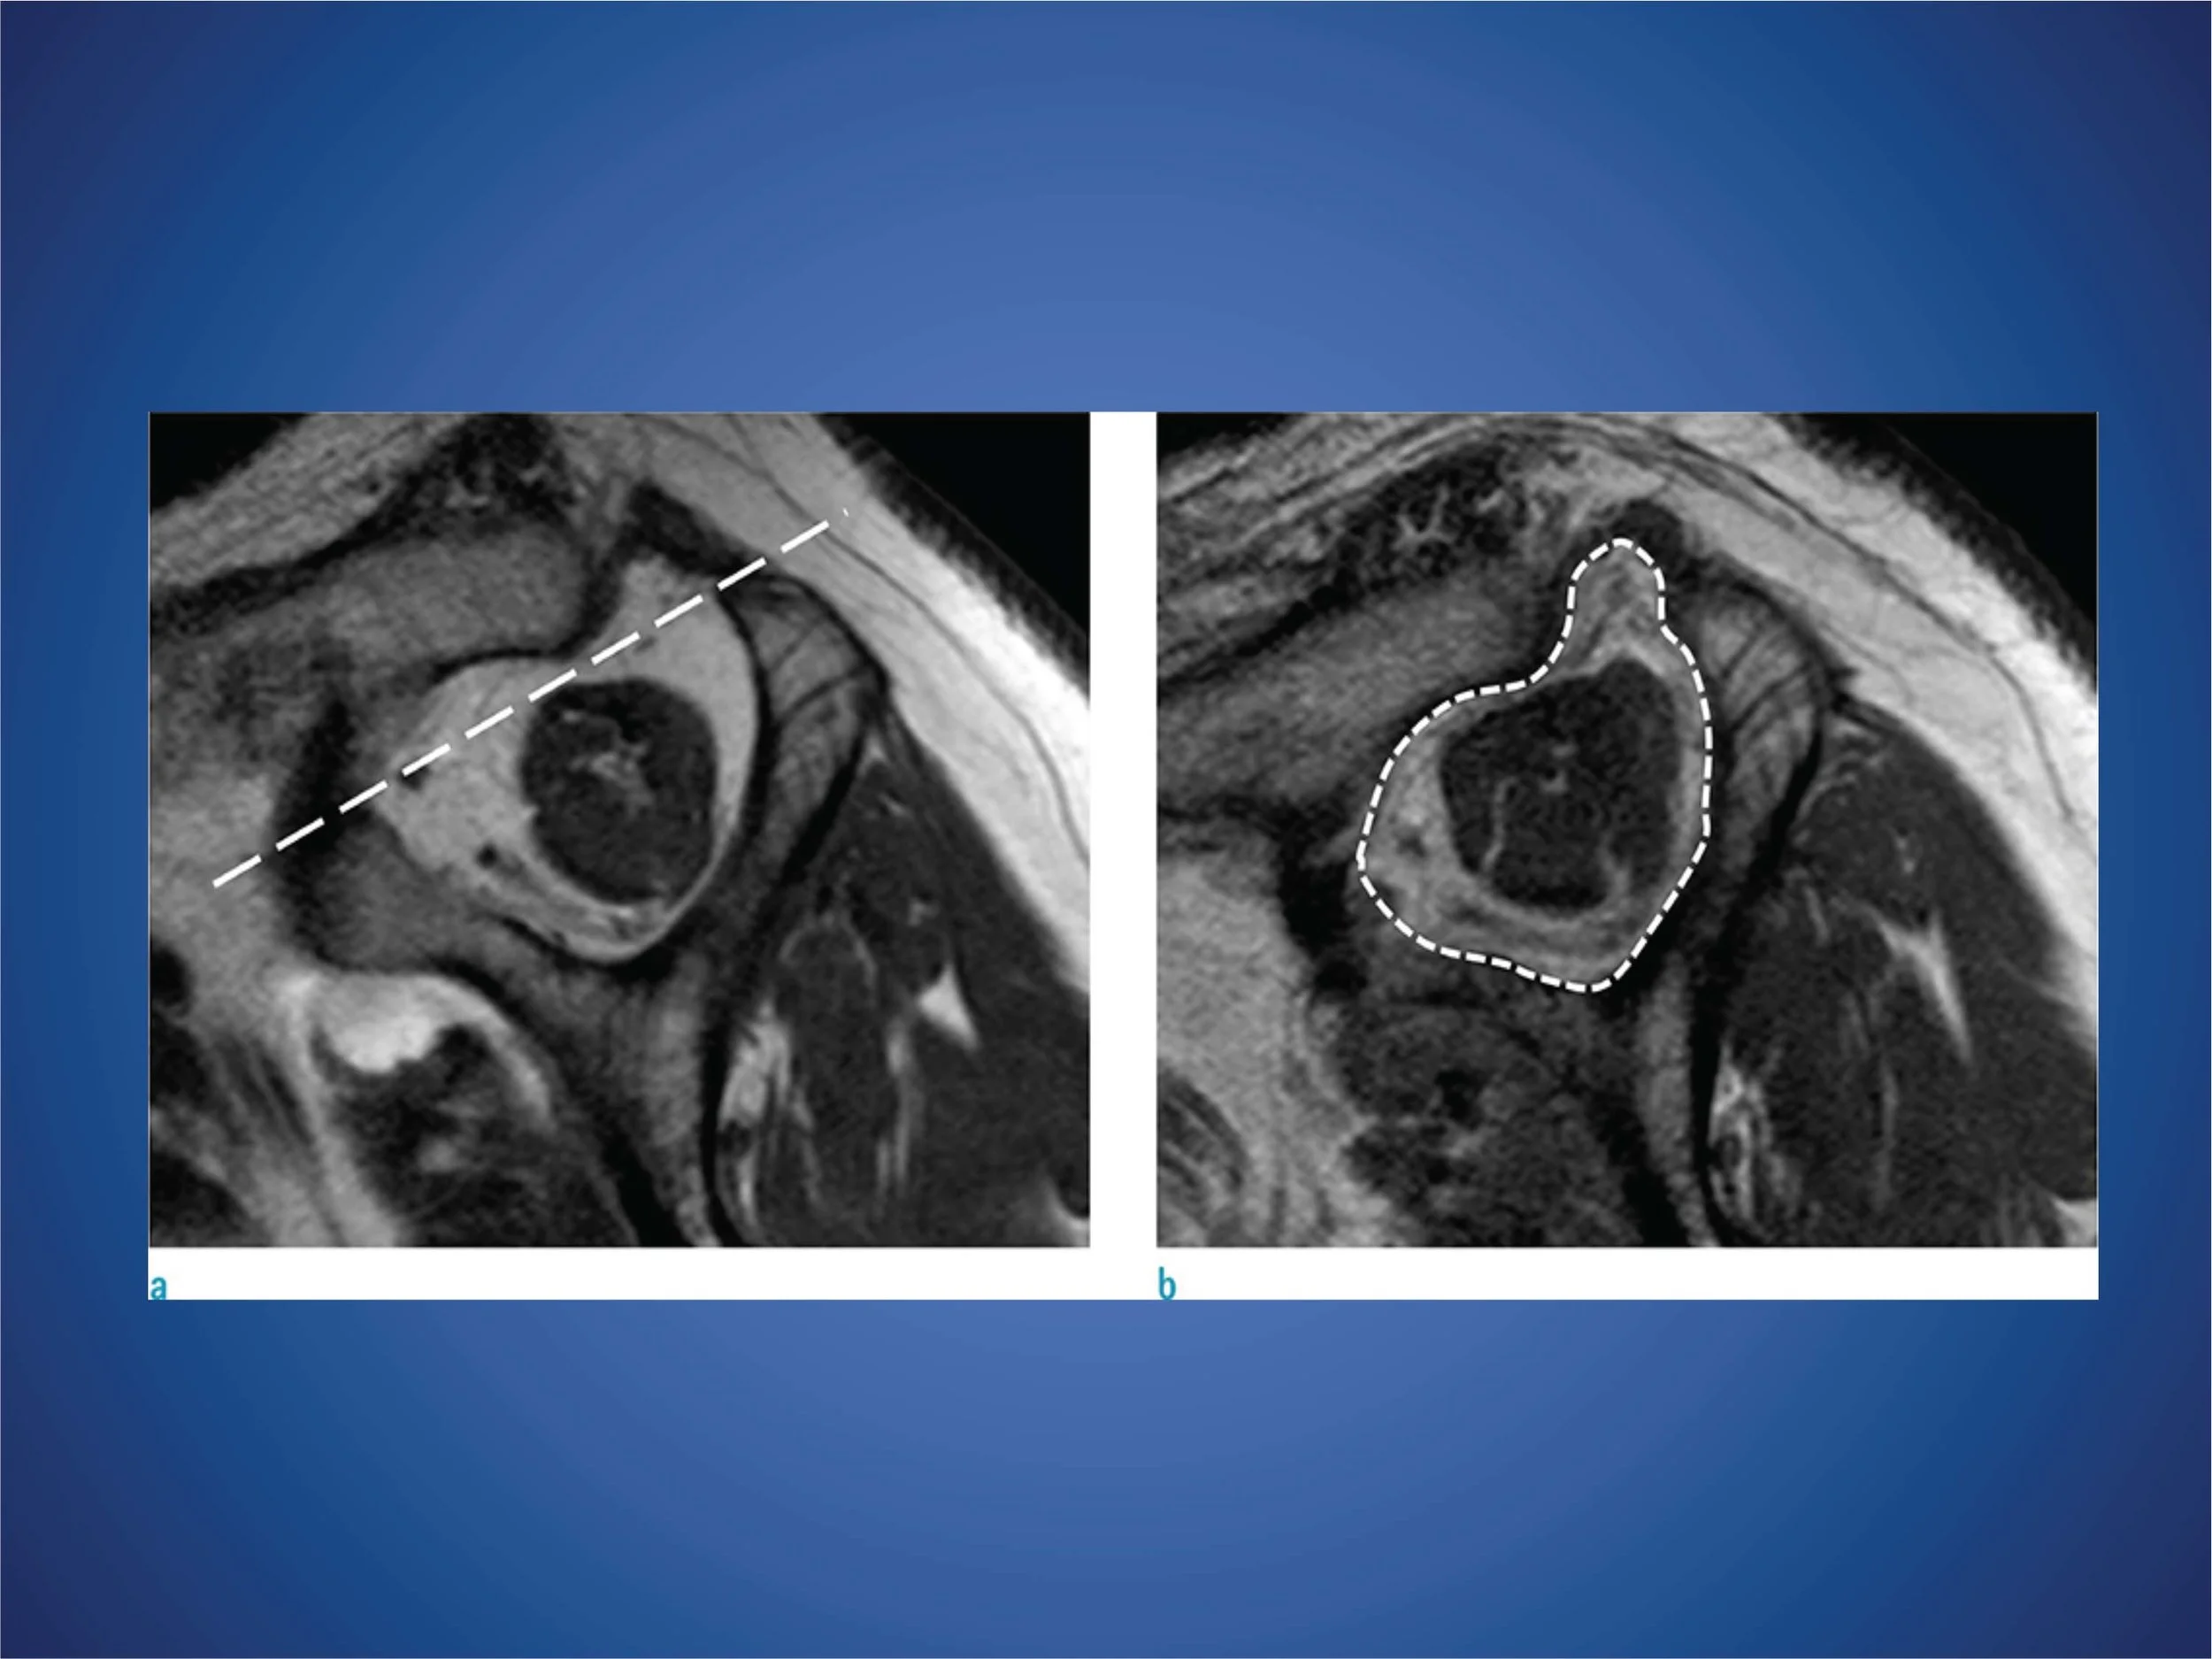

Rotátorköpeny Rekonstrukicó